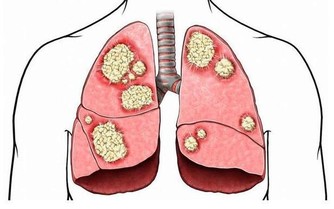

它們是一些抗氧化劑,如維生素E、維生素C、β胡蘿蔔素、類黃酮等。維生素E是重要的自由基清除劑,能阻止脂質的過氧化作用。越來越多的證據表明,人體血管壁發生的脂質過氧化作用,可造成動脈粥樣硬化,導致卒中和心肌梗死。維生素C有多種抗氧化特性,特別是在呼吸道,可去除有氧化作用的空氣污染物的毒性。隨著年齡的增長,人體的自由基清除能力有所下降,這時需要補充一定的抗氧化劑,以延緩衰老和維護健康。